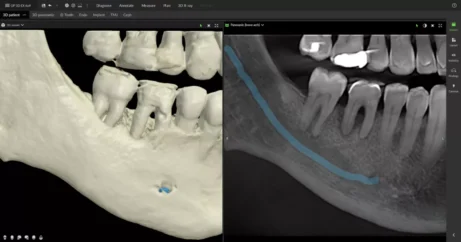

Zavedení implantátů

OP 3D EX a DTX Studio™ Clinic vám umožňují rozšířit klinické možnosti díky vícenásobným pohledům na snímky pacienta, předoperačnímu posouzení anatomie a podpoře přesného a bezpečného zavádění implantátů.